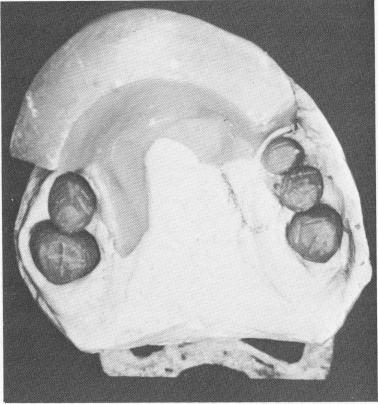

Fig. 15-9. Metal copings are seen on articulated master casts. Note the extreme prognathic appearance from the limited anterior growth of the maxilla.

3 Metal copings for implant prosthesis seen on articulated master casts